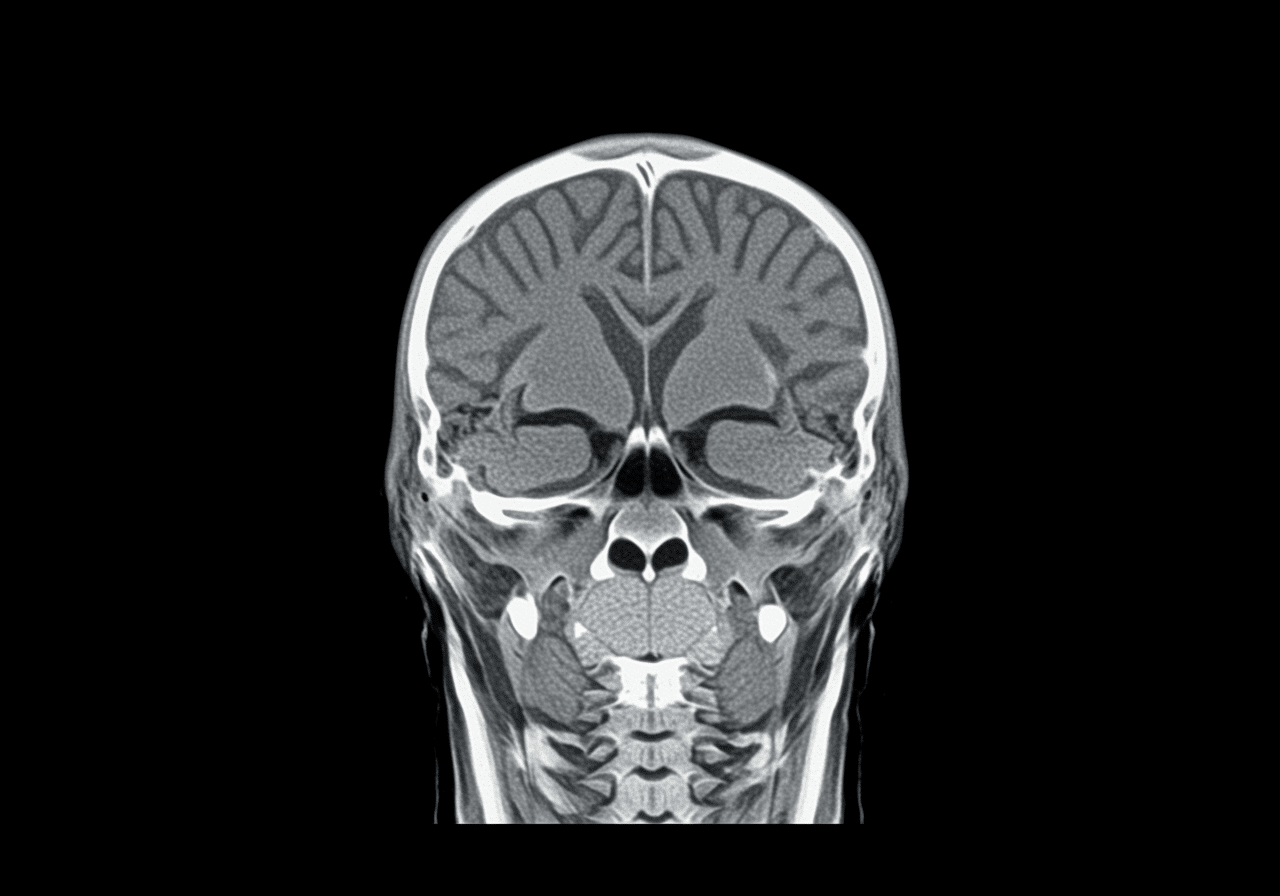

Emergency CT scanner room at Priority ER Odessa for head imaging

State-of-the-art CT imaging equipment available 24/7 at Priority ER for immediate head scans